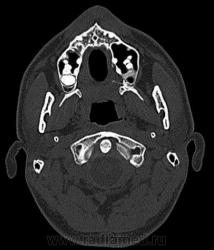

Два случая....

1. Эктопия зуба?

2. Хронический гайморит?